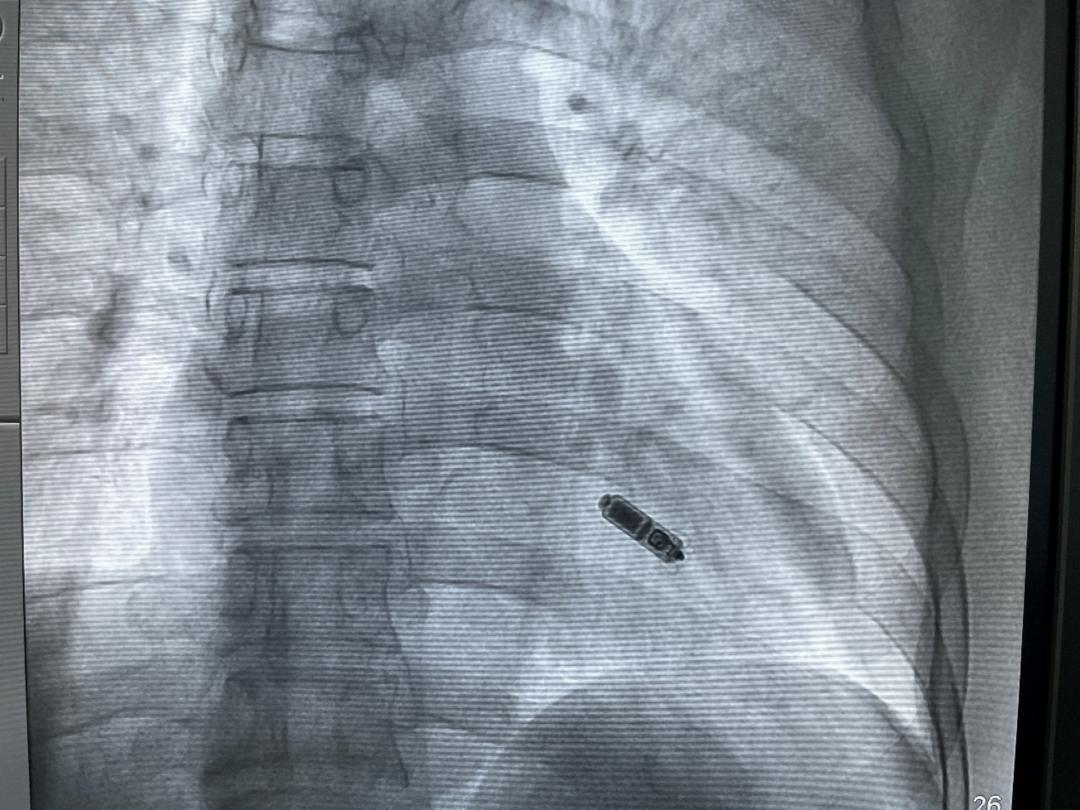

鉴于患者病情危及,急需植入起搏器。患者及家属担心植入传统起搏器带来感染风险,同时也希望起搏器术后外观得体,不影响日常生活。为此,在全方位分析了患者情况后,心内科副主任彭景添、张智亮等为患者定制了缜密的手术方案,决定采用新一代Micra AV无导线双腔起搏器。该起搏器无需植入电极导线,也无需在胸前皮下制作囊袋,体积仅有0.8CC,重量仅约2克,兼容1.5 T/3.0 T全身核磁共振扫描检查,手术过程时间短,植入成功率高,能够有效解决外表不美观、感染风险大等忧虑。

30分钟左右,心内科团队为患者完成手术,患者术中电学参数良好、术后反应良好。“两天后,患者就可以恢复正常的工作和生活,该技术实现了无线起搏治疗领域的升级再突破。”张智亮介绍道。